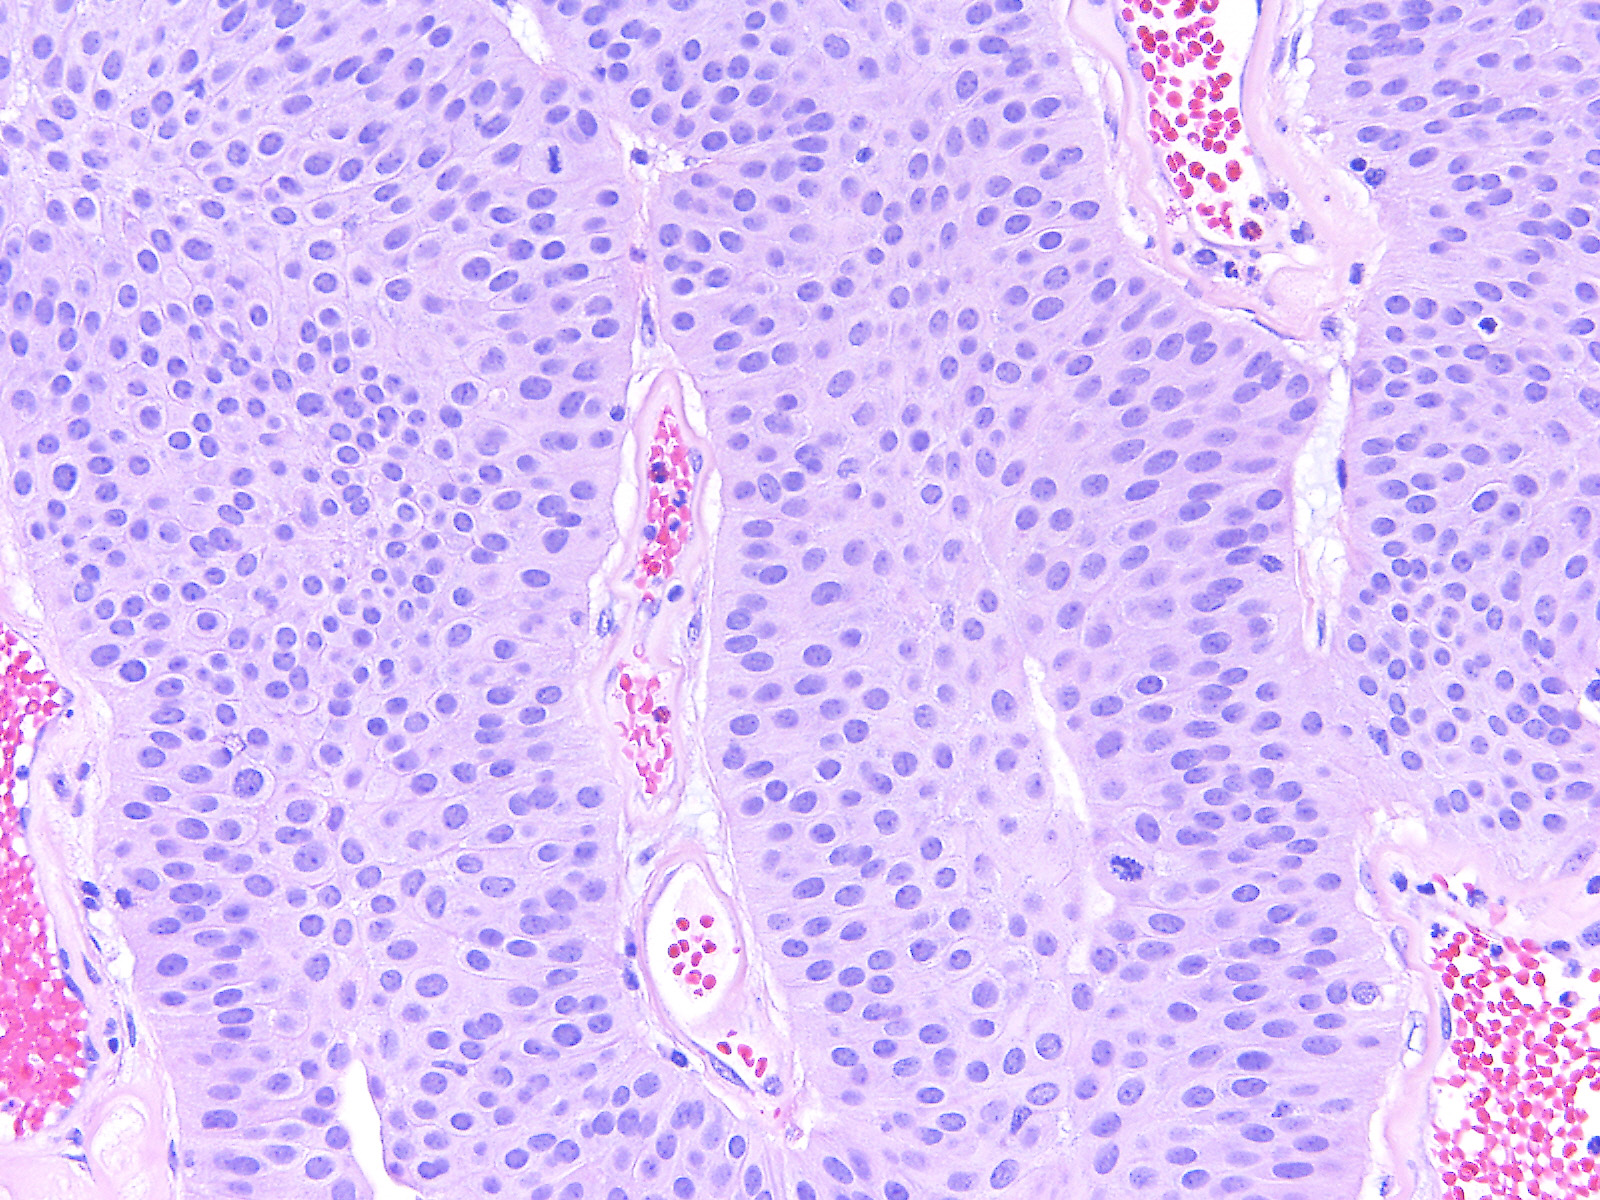

Consensus grade: Low-grade papillary urothelial carcinoma (LG-PUC)

PULMP can be discussed, but mitosis, and I don't like PUNLMPs with mitosis, although in the initail description they have been mentioned |

A 74 year-old woman underwent a TURBT.